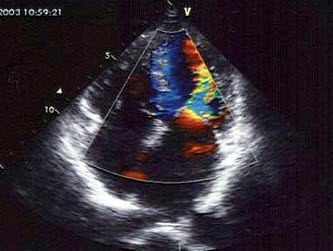

47、单项选择题

该病例最有可能诊断()

A.肺动脉内径增宽

B.动脉导管未闭

C.肺动脉瓣狭窄

D.肺动脉瓣关闭不全

E.右室流出道狭窄